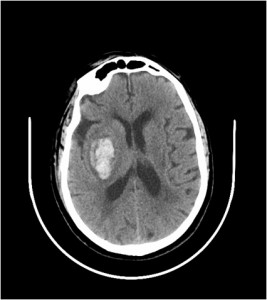

Un ictus es un trastorno de la circulación cerebral que ocasiona una alteración transitoria o definitiva del funcionamiento de una o varias partes del cerebro. Un ictus puede ser hemorrágico o isquémico. Lo primero que tenemos que hacer es descartar ante qué tipo de ictus estamos, isquémico o hemorrágico. Podríamos usar una tomografía axial computorizada o TAC y la resonancia magnética o RM. La principal ventaja del TAC sobre la RM amplia disponibilidad, rapidez. Además de detectar la hemorragia, la TC permite detectar signos precoces del infarto (hipoperfusión y edema) y el diagnóstico diferencial con otras lesiones como neoplasias.